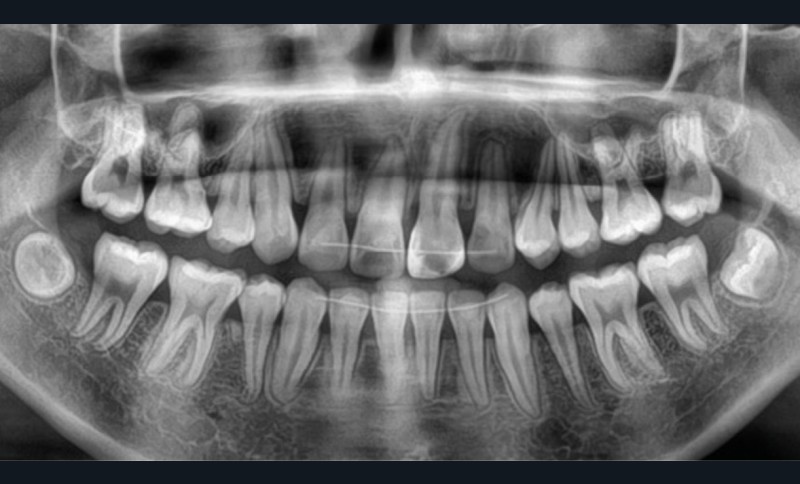

Une patiente âgée de 12 ans se présente en consultation, motivée par la position de son incisive centrale maxillaire, décrite comme « en avant », marquée par une dyschromie et une mobilité de grade 2 selon Muhlemann. L’examen clinique montre l’absence de 23 sur l’arcade, une dysharmonie dents-arcade marquée, un surplomb accentué, et une déviation des milieux inter-incisifs, conséquence du comblement spontané de l’espace de 23. L’ensemble s’inscrit dans un contexte de Classe I d’Angle molaire. L’orthopantomogramme révèle l’inclusion de 23, associée à une résorption radiculaire étendue aux deux tiers de 21. La 22 ne présente aucune altération visible.

La patiente, de profil normodivergent, présente une Classe I squelettique sans troubles fonctionnels (fig. 1-8).